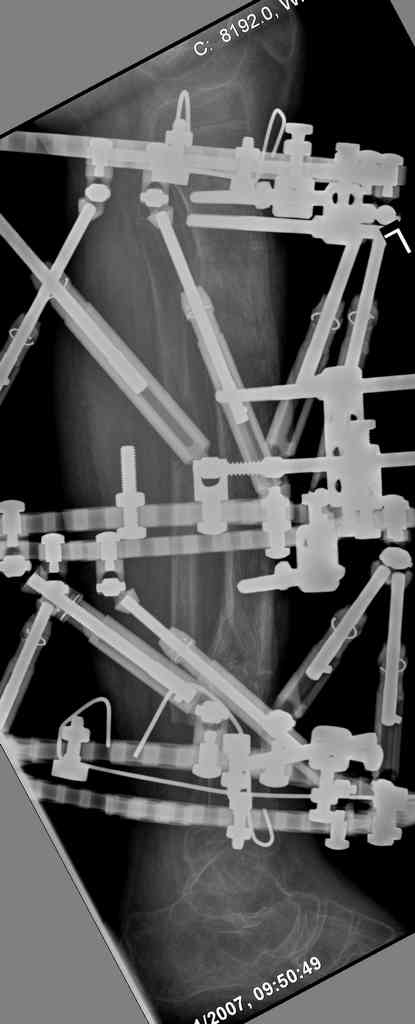

Re: case tibial defect

Another choice is simply perform shortening + posterior angulation with Ilizarov or TSF , than gradual correction of the angulation.After all apply third ring on the proximal tibia and start lengthening.

We had recently similar case in 14 years old boy with 45 mm bone defect after open tibial fracture.Boy doing excellent .This technique is not new, Sasha Lerner did it in Rambam , Rozbruch wrote also.

Another advantage of this techniqe is relaxation of soft tissue and possibility for closure even large defects of the skin.In your case I will apply ring on the foot and mid diaphysis of the tibia ,removal of the fibular plate,sindesmotic wire, and after correction of angulation on the proximal tibia.